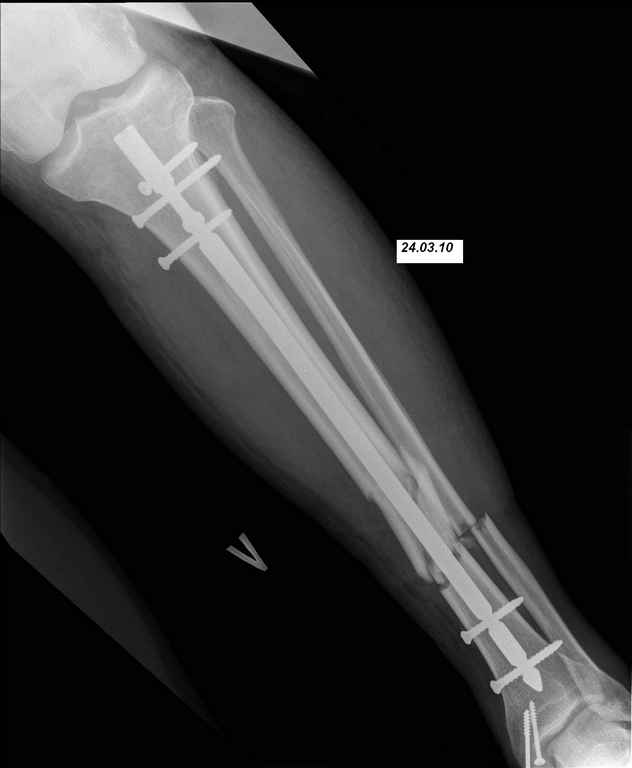

24.03.10 выполнены операции - БИОС перелома большеберцовой кости левой голени (штифт Synthes), остеосинтез перелома внутренней лодыжки левой голени винтами. Послеоперационный период протекал без осложнений. Выписан на 10 сутки. Амбулаторно не наблюдался.

07.04.10 госпитализирован с диагнозом: Нагноение парафрактурной гематомы. При поступлении отек, болезненность при пальпации, гиперемия кожи по передней поверхности, пальпаторно флюктуация в месте перелома, местное повышение температуры кожи. выполнена пункция гематомы, получено 40 мл гнойно-геморагического пунктата. Взят бак посев (S. aureus, чувствительный ко всему что у нас есть). В место флюктуации введен раствор Новокаина 1%-30 мл+Гемтамицина 2,0 мл. Сформировался свищ в месте пункции, который закрылся через 10 дней. Проводились внутрикостные инъекции антибиотика (Кламосар, полусинтетический пенициллин, бета-лактамный) в левую пяточную кость №10. Температура за период госпитализации не выше 37,2С. По анализам небольшой лейкоцитоз. Свищ закрылся, локально гиперемия, отек, местное повышение температуры регрессировали. Выписан. И опять пропал. Травмполиклинику не посещал, на контрольные осмотры к лечащему врачу не приходил.

И вот опять объявился. Снимки и фотографии в приложении(первичные потеряны). Около 1 месяца назад появились боли в области нижней трети голени в проекции дистальных блокирующих винтов, передвигался с нагрузкой 50% (сам для себя так решил, сам себе разрешил). Путешествовал по Волгоградской области, обратился к травматологу, со слов перевязывали, лечили антибиотиками. Лучше не стало. Вернулся домой.

Вчера госпитализирован в отделение. Локально умеренный отек, кожная температуа не повышена. По передней поверхности в области дистального блокируюшего винта свищ, скудное гнойное отделяемое, винт удален на перевязке зажимом. «Старый» свищ не функционирует. Взят бак. посев, ждем результат.